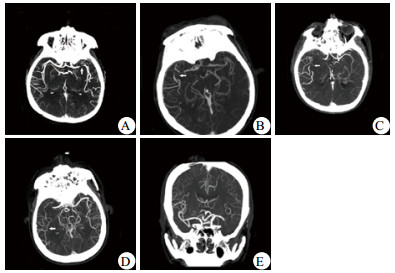

1.2 方法共有153例急性脑梗死患者完成绿色通道治疗,本研究入选标准为其中头颅CTA显示颈内动脉(internal carotid artery, ICA)或大脑中动脉(middle cerebral artery, MCA)梗死者。排除标准为既往存在严重的心肺不全或遗留神经功能缺失。按该标准,共有94例患者纳入研究。本研究观测终点为再通治疗后30 d,近期预后改善指符合以下全部标准:期间患者存活、未发生症状性脑出血,并且30 d NIHSS评分较治疗前提升 > 4分[9-10],否则认为近期预后不良。研究患者的相关临床因素,分析引发不良预后的危险因素。纳入的临床因素包括年龄、性别、既往史(房颤、高血压、糖尿病)、治疗时间、治疗方式、梗死部位、侧支循环状况。部分因素的定义区分如下:年龄高低以≥70岁或 < 70岁区分;治疗时间指从症状出现至首次进行溶栓或介入治疗的时间,时间早晚以 < 4 h或≥4 h区分;治疗方式分为仅溶栓、仅介入、溶栓衔接介入治疗;梗死部位指闭塞或狭窄部位发生在ICA或MCA;侧支循环状况参照软脑膜侧支评分(pial collateral score)[11]:1分-闭塞血管的远端部分有侧支循环重建;2分-侧支重建血管出现在与闭塞血管相邻的近端部分;3分-侧支重建血管出现在与闭塞血管相邻的远端部分;4分-侧支重建血管出现在闭塞血管两段远端;5分-闭塞血管支配区无或仅有较少的侧支血管重建。以1~2分为侧支循环良好,3~5分为侧支循环不良[10], 见图 1。

| A: 1分,左侧大脑中动脉M1闭塞,M1远端重建;B: 2分,右侧大脑中动脉M1闭塞,M2近端重建;C: 3分,右侧大脑中动脉M1闭塞,M2远端重建;D:4分,右侧大脑中动脉M1闭塞,M3分支重建;E: 5分,左侧大脑中动脉M1闭塞,其支配区仅有少量血管重建。箭头示侧支重建血管出现位置 图 1 软脑膜侧支评分 Figure 1 Pial collateral score |